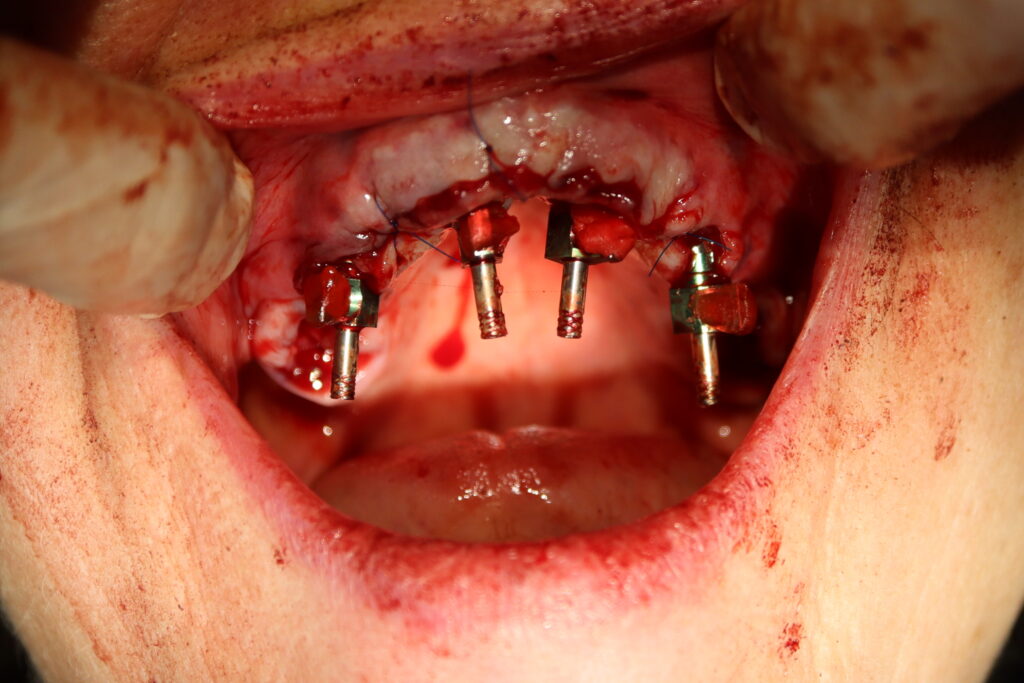

На верхней и нижней челюстях были удалены зубы и проведена комплексная имплантация по системе All-on-4, установлены 8 имплантатов Osstem.

Спустя 7 дней на обеих челюстях зафиксированы металлоакриловые протез из 12 зубов.

процесс имплантации

Это фото может содержать тяжелый для восприятия контент